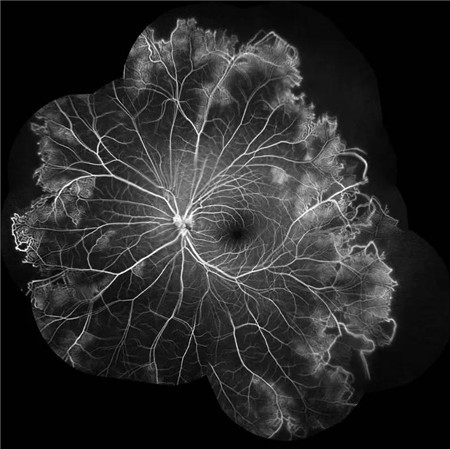

特发性视网膜血管炎、动脉瘤和视神经视网膜炎综合征(Idiopathic Retinal Vasculitis, Aneurysm, and Neuroretinitis syndrome,简称IRVAN综合征)是一种病因不明的较为少见的视网膜血管炎性疾病,此病症常在30-40岁发病且多为女性发病。在发病的前期,如果进行及时有效的治疗干预,预后效果多数较好。但一拖再拖,错过最好的治疗时间,可引起严重的并发症。在这里提醒大家,一定要密切关注自己眼部突发情况的出现,警惕眼前突然发生黑影飘动,视力下降的情况,尽早就医。

视盘附近的动脉和动脉分叉处出现瘤样动脉扩张,视盘充血,边界不清,引起视盘周围视网膜内硬性渗出;视盘周可有少量放射状出血。

静脉不规则扩张和血管鞘膜,周边部小血管广泛闭塞,交界处毛细血管扩张和异常吻合。

严重者可发生从周边到黄斑的血管闭塞和缺血、玻血、新生血管性青光眼,最终视神经萎缩。

长期追踪发现动脉瘤是一种血管炎性的游走性改变,炎症消失时,血管壁强度恢复,瘤体减小,甚至恢复正常。